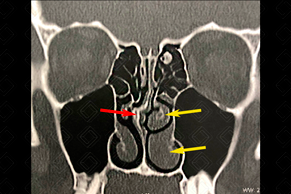

Texto alternativo para a imagem Figura 4. Créditos: Dra. Elazir Mota - Rio de Janeiro/RJ

Descrição da figura 3 e 4: Tomografia computadorizada dos seios paranasais evidenciando desvio da porção cartilaginosa do septo nasal para a esquerda (seta vermelha) e da sua porção óssea, visualizada nos cortes mais posteriores (seta amarela). Note ainda o preenchimento das células etmoidais e espessamento mucoso nos seios maxilares.